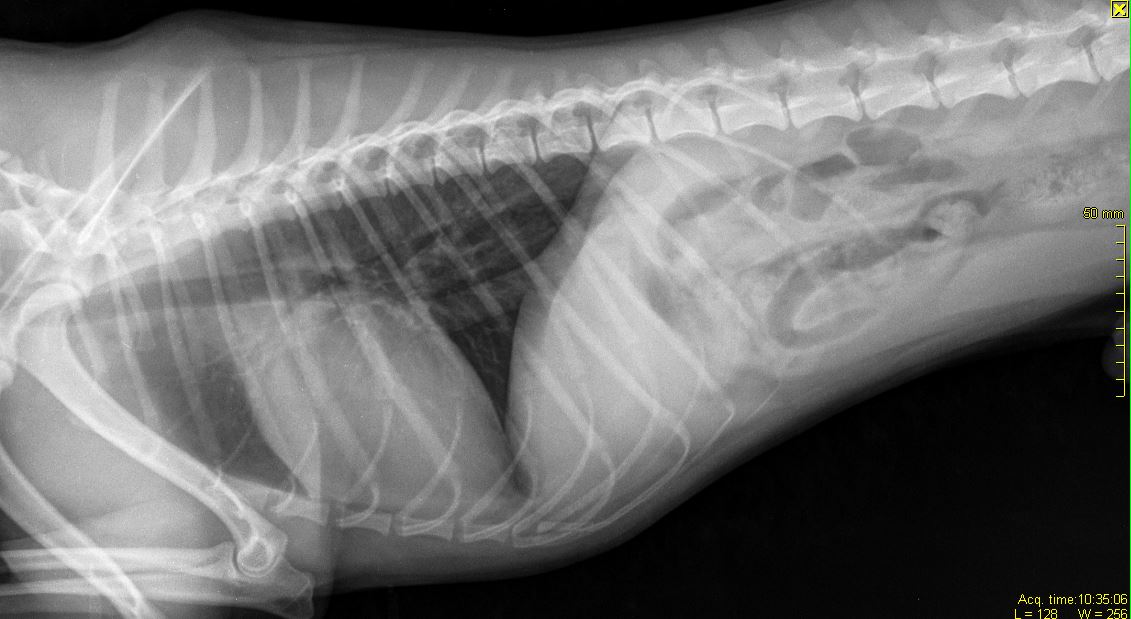

Прикладываю снимки, приблизила, чтобы лучше видно было. Также выкладываю снимок грудной клетки(этот снимок мы делали пару месяцев назад, когда он кашлял и врач исключал бронхит), на нем тоже есть ТБС, вдруг тоже на нем что-нибудь видно..

Снимки:

Название: 04.02.2018 Джин общий снимок.JPG

Просмотров: 736

Размер:	31.1 Кб

В том то и дело, что я вывиха не вижу... Потому и сомневаюсь... пересмотрела наверное больше сотни разных снимков собак с вывихами, дисплазиями и другой ерундой, но на нашем снимке головка бедренной кости находится в вертлужной впадине, никаких наростов на ней нет, сама вертлужная впадина выглядит как глубокая чашка, а не как блюдце (которое описывают при дисплазии).. Потому и сомнения:(((

По сабжу. Переделывайте рентген - собака лежит как черти что. Должна лежать прямо. Конечности должны быть строго параллельны, рентген ТБС делается с оттяжкой. Тогда можно будет говорить о корректных снимках (и только о них). О каких связках речь, если они на рентгене не видны? Для того, чтобы разглядеть связки вообще - делают КТ либо МРТ.

именно вывих, но коленной чашечки.

Даже при этой раскладке явно видно, что вывиха тбс нет.